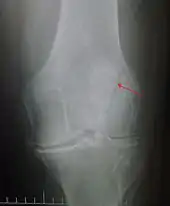

كسر رأسي بالرضفة و السهم الأسود يشير إلى خط الكسر.